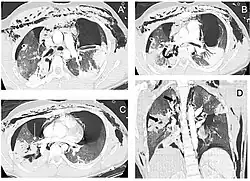

| Reconstruction of the trachea and bronchi with x-ray computed tomography showing disruption of the right main bronchus with abnormal lucency (arrow)[1] | |